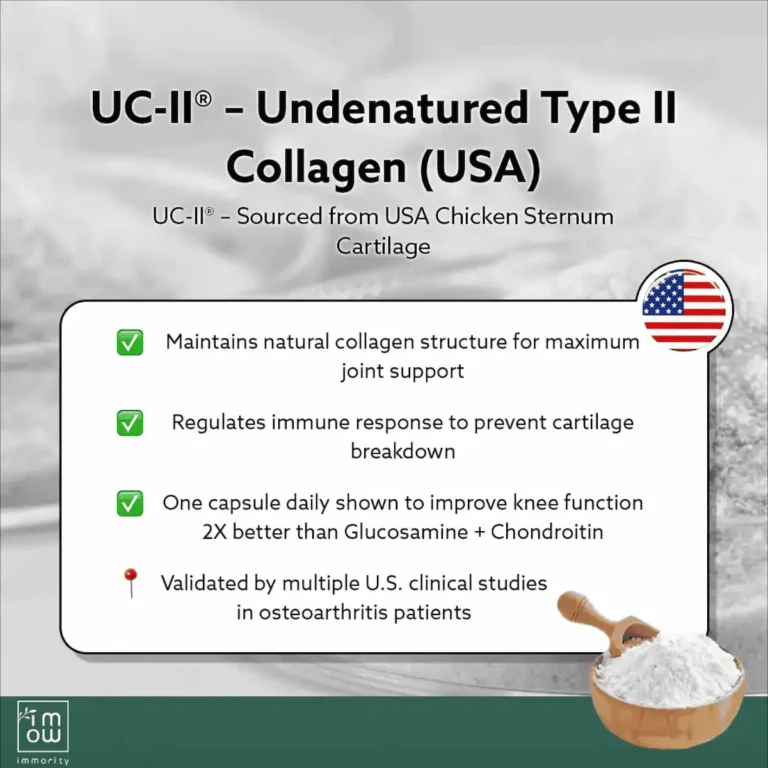

A patented Type II Collagen, sourced from chicken cartilage from USA.

- Rebuild and reduce cartilage & Joint Fluid Loss

- Relieve Pain & Restores joint flexibility

- Proven to be 2x more effective than glucosamine + chondroitin